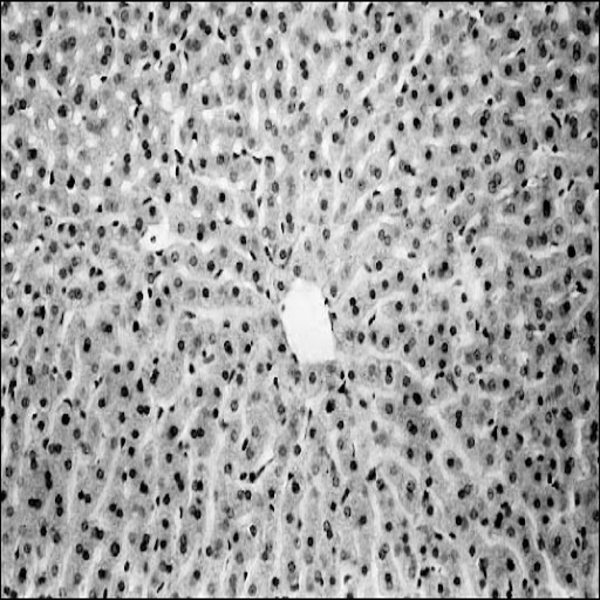

- Preparation of paraffin and frozen tissue sections in different sizes

- General and specialized tissue and cell staining

- Prepare educational slides for students from all available tissues

Histological methods includes sample processing in the pathology laboratory, preparation of the slide and its examination under a microscope, sample fixation, molding, microtome cutting, staining and assembly of the slides.